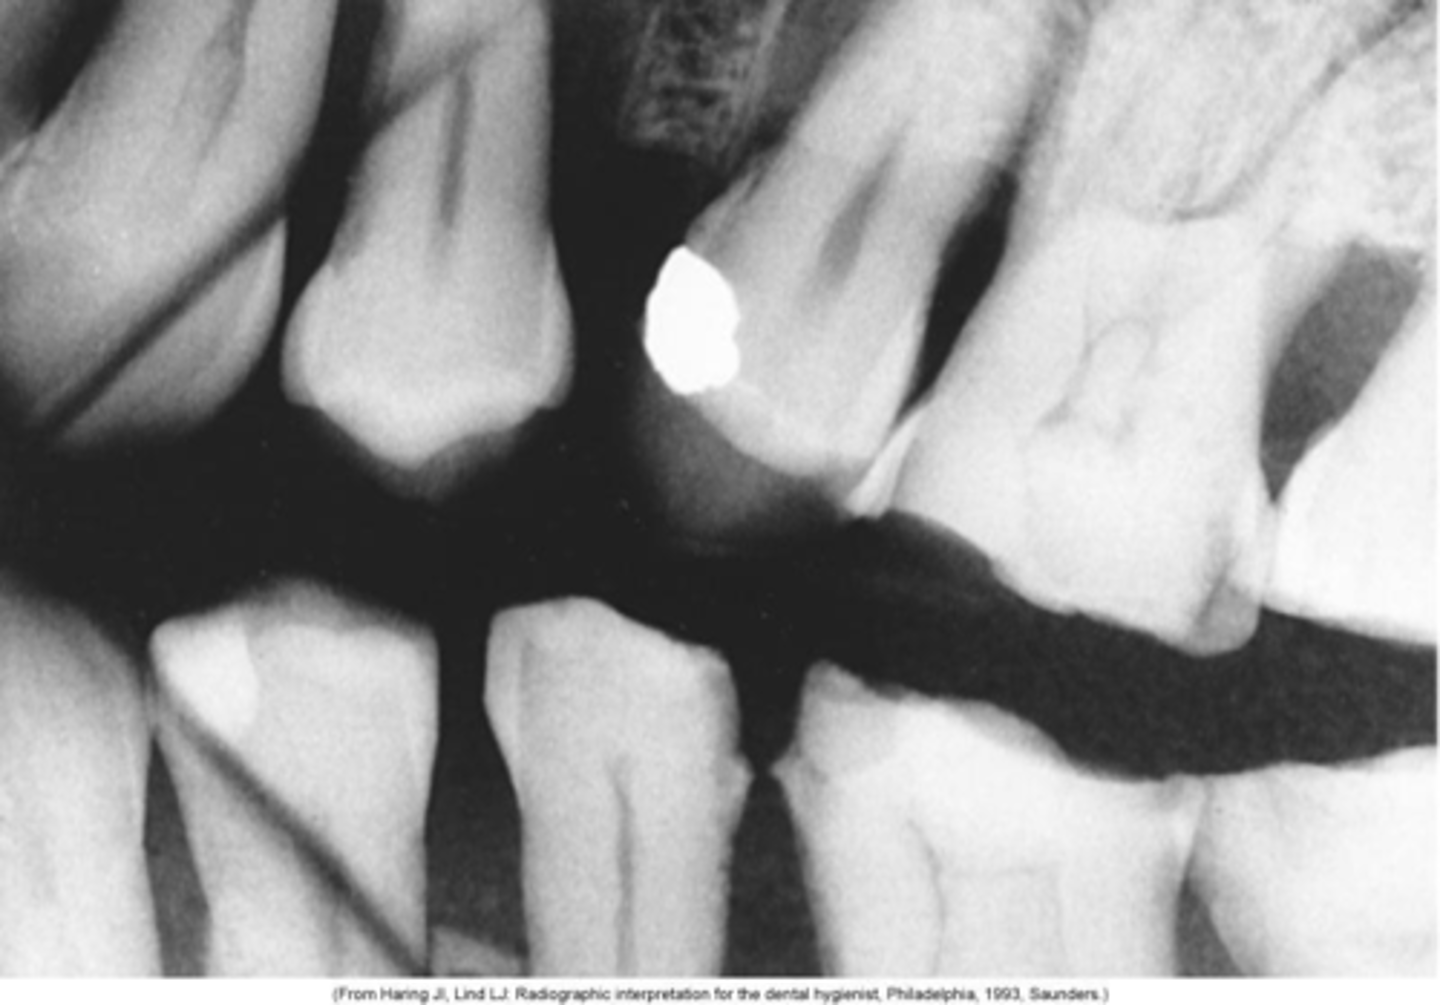

Cone cut, rotation

What is this error?